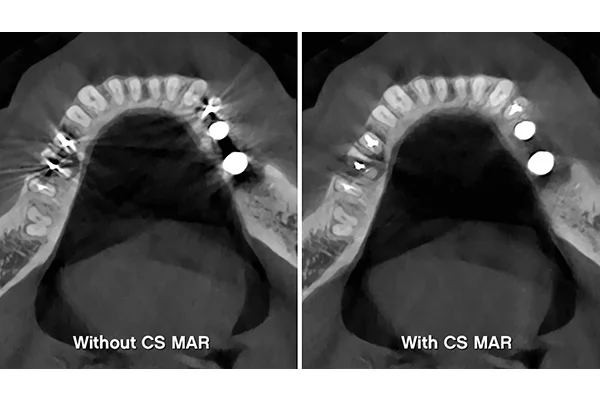

• MAR patentované potlačení artefaktů s živým náhledem efektu filtru pomocí nezávislého algoritmu 3D (zcela unikátní)